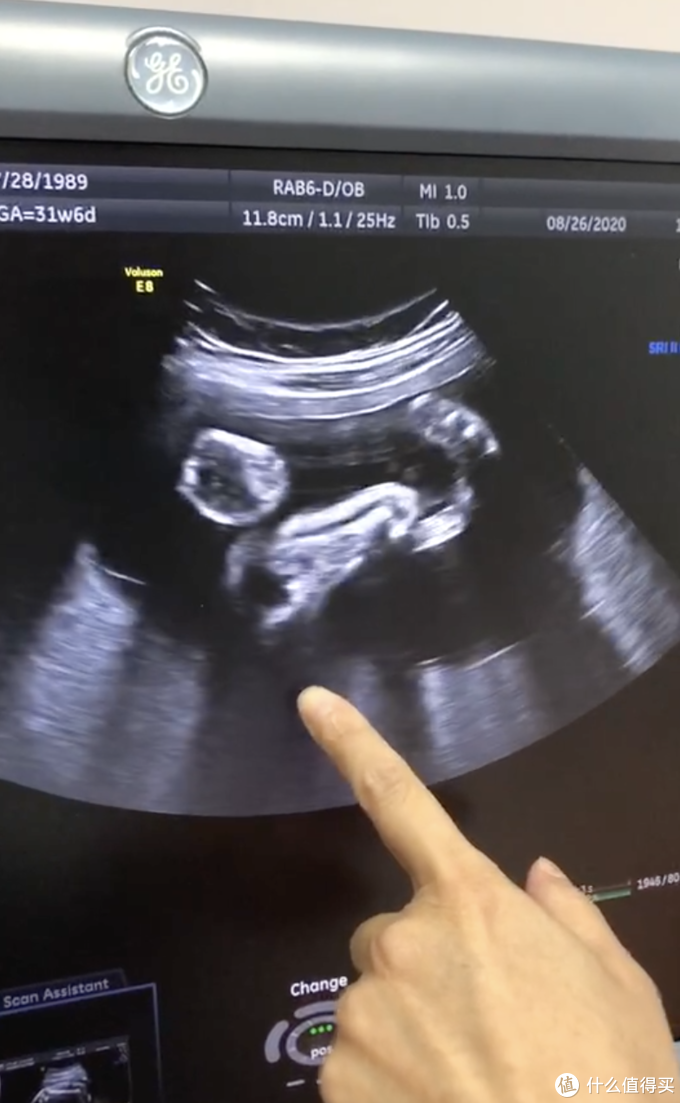

产检中经常要做的超声检查,是我觉得区别公立医院最优的项目:

- 家人可以陪护在旁,尤其是做大排畸等检查,家人可以一起观看讨论;

- 医生讲解非常细致;

有专门提供给孕妇看的屏幕,这样就不用扭头了,非常贴心。

私立医院的服务都体现在细节上,比如b超检查在医生来之前,护士会用布遮住你的肚皮以免太凉;使用的是一次性的床垫,干净卫生(不会有人冷冰冰催着你说“自己拿一张垫上去,快点”);用的耦合剂是一直温着的,擦到肚皮上的时候不会一下子【透心凉】,尤其是在冬天,体感非常明显,公立医院则是顾不上这些了。

另外产检的超声检查很多都是做排畸的检查,每次做心里都很紧张的,但是有医生在旁边温和地讲解,心情会放松不少。每一次医生都会很详细地和我说(并且是说听得懂的人话):这里是宝宝的头发,你看漂起来了因为是在羊水里;这里是头顶朝下看,刚好看到宝宝的耳朵;这里是宝宝的手脚,在左边,所以你应该是左边胎动比较厉害……

家属在边上也可以很方便地和医生交流、询问,整个超声检查不紧不慢,非常舒适。